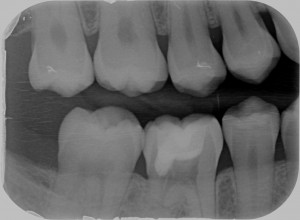

Sì, perchè ora faccio il figo, ma nel non lontano 2011, mi arriva una paziente con questo dente.

Cosa caspita era capitato a questo dente? Allarmato faccio vedere la radiografia a Federico, il mio socio, e anche lui pensa a qualcosa di brutto. Che so, un tumore di quelli incomprensibili che avevamo studiato solo sui libri di radiologia che si era insinuato all’interno di questo 4.6! ???

Quando nel 2013 mi è arrivato all’attenzione questo caso

La prima: i riassorbimenti esterni non sono rari, ma solo difficili da diagnosticare nelle fasi precoci perché assomigliano a carie.